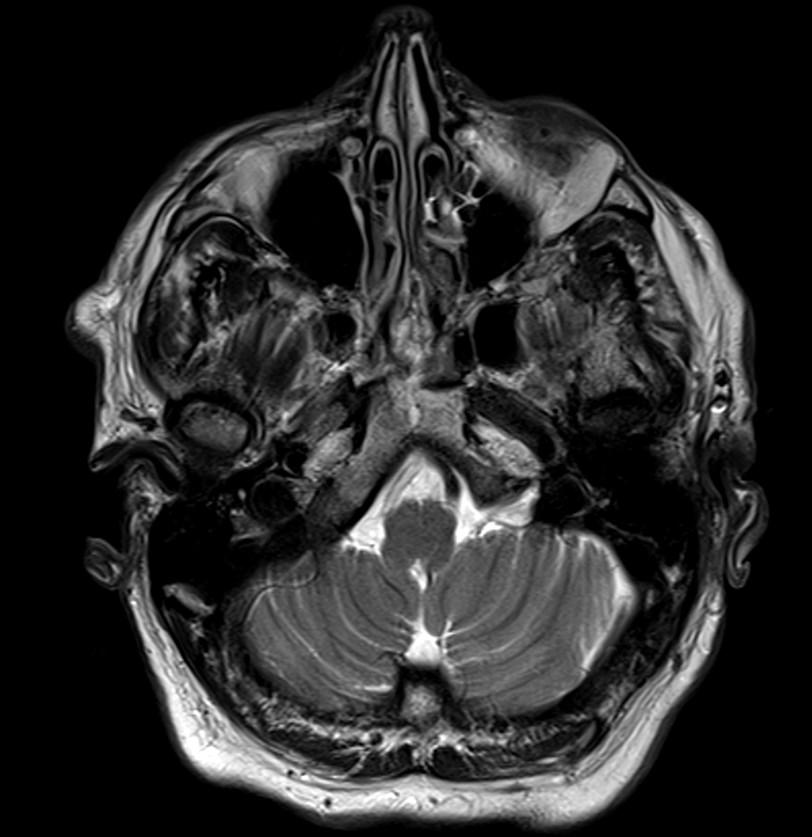

Loss of the signal void was detected on the right vertebral artery on the axial T2 weighted image (arrows).